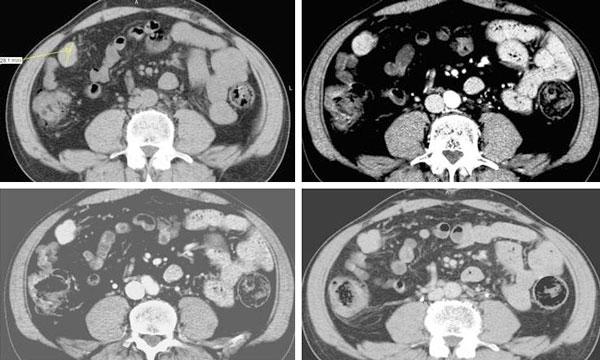

A 56-year-old man with history of persistent hematuria from bladder cancer was referred to our Institution for suspected peritoneal carcinosis. For staging purposes he underwent abdominal computed tomography and ultrasound. The integration of patient's history and imaging results led to the diagnosis of peritoneal splenosis. The patient therefore underwent regular Trans Urethral Resection of Bladder for the known malignancy; while no treatment was necessary for splenosis. Two years follow-up was negative for metastases.

一名56岁男性,有膀胱癌导致持续性血尿病史,因疑似腹膜癌转移被转诊至我院。为进行分期评估,他接受了腹部计算机断层扫描和超声检查。综合患者病史和影像学结果,诊断为腹膜脾组织移植。因此,该患者因已知的恶性肿瘤接受了常规经尿道膀胱肿瘤切除术;而脾组织移植无需治疗。两年随访未发现转移。